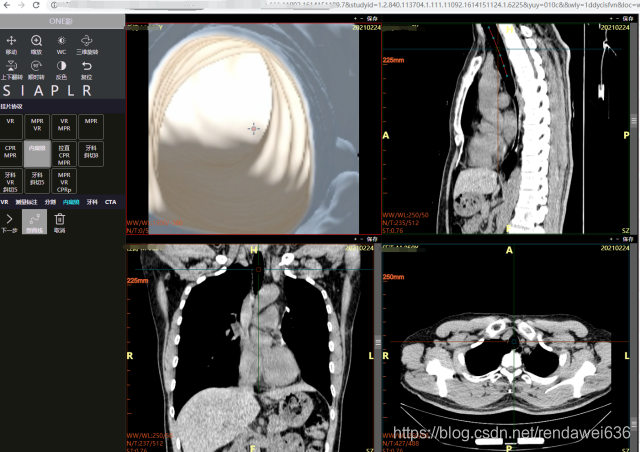

3 实验效果

下图是气道的一个虚拟内窥镜图